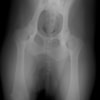

左後肢の挙上を主訴に来院されました。触診にて両関節の前方引き出し兆候、両膝蓋骨の内方脱臼を認めました。関節液検査より免疫介在性多発性関節炎は否定的でした。レントゲン検査にてfat pad signを伴う関節炎が認められたことから、前十字靭帯断裂と膝蓋骨内方脱臼(左GradeⅢ 右GradeⅢ〜IV)併発と診断し、手術を行いました。

術前正面像

術前のTPAは左後肢33.1°右後肢26.8°でしたがTPLO実施により左後肢5.5°右後肢12°に矯正されました。